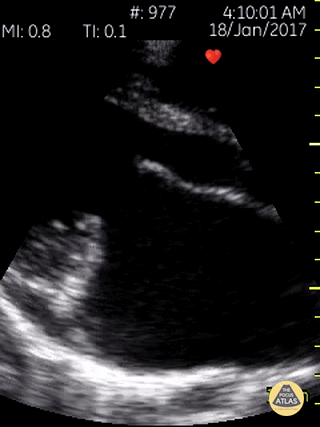

Mitral stenosis with mitral regurgitation with the classic MV "hockey stick" sign of rheumatic mitral valve disease. Dr. Gordon Johnson MD Internist Portland Oregon & Uganda